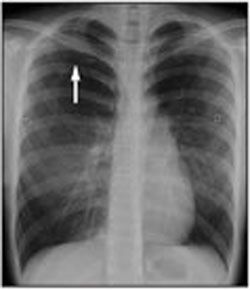

The chest radiograph shows a moderate pneumothorax on the right (Figure 1).

The presence of pneumothorax is usually confirmed by plain chest radiographs. A visceral pleural line without vessel markings is a key diagnostic finding.3 Radiographs may also show hyperlucency of vascular and lung markings. Chest CT can help distinguish preexisting lung conditions, such as neoplastic disease, from spontaneous pneumothorax when the diagnosis is uncertain.2,4

In this patient, a pigtail catheter was used to aspirate air from the pleural cavity; serial chest radiographs performed over the following days showed gradual lung re expansion (Figure 2). She was discharged after 7 days and was scheduled for follow-up with her primary care physician.